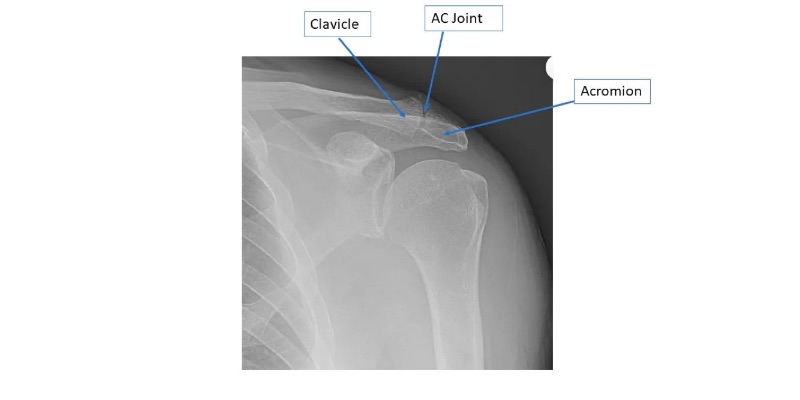

Clavicle arthritis x ray by Orthopaedic Associates of Muskegon

Shoulder radiographs demonstrating "AC" arthritis.

Distal Clavicle (AC) Arthritis

Distal clavicle or "AC" (acromioclavicular) arthritis results in pain over the shoulder, especially right on top of the shoulder with overhead and cross body maneuvers. Sometimes pain from AC arthritis can be present in addition to rotator cuff pain or a completely separate issue. Pain from the AC joint is usually quite distinct from rotator cuff pain but they can be confused. Arthritis of the AC joint is initially treated with physical therapy, NSAIDs, and cortisone injections. When these measures fail to help, a limited distal clavicle resection surgery can be performed to open up the space between the clavicle and acromion. This can be performed arthroscopically and requires only a few days of immobilization afterwards.